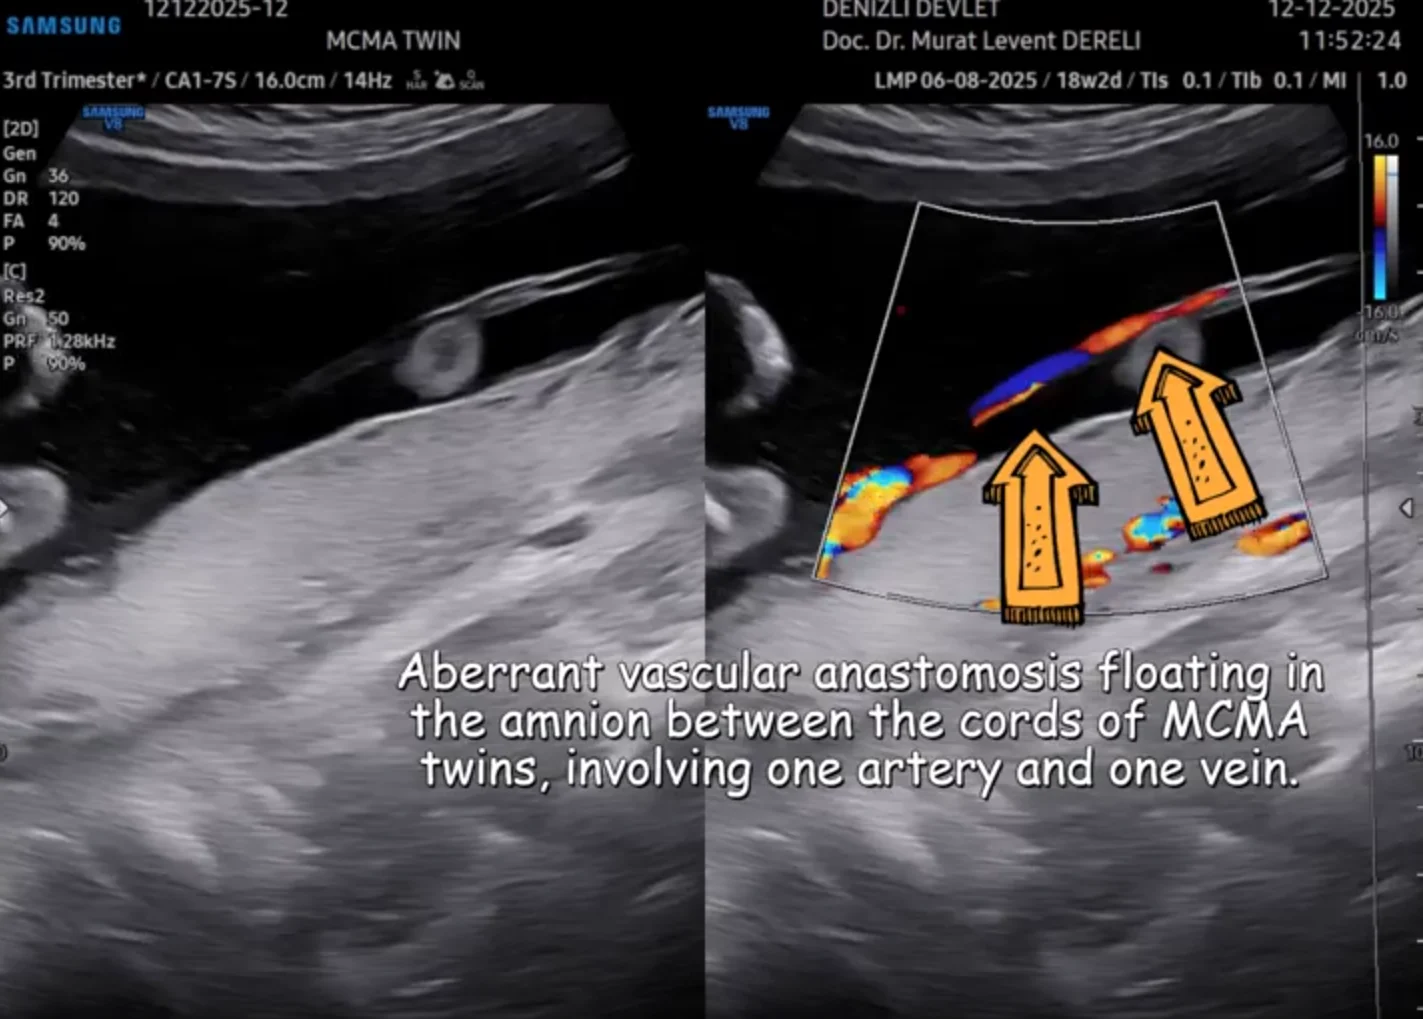

“Monochorionic-Monoamniotic Twin with Aberrant Vascular Anastomosis:

(Monoamniotic twin with abnormal vascular anastomosis)

In addition to sharing a single placenta, the circulatory systems of monochorionic twins may be connected by random vascular anastomoses. This can cause disproportionate blood flow and lead to twin-to-twin transfusion syndrome (TTTS).

In monoamniotic twins (identical twins in a single sac), the most significant risk is entanglement of the umbilical cords, which can decrease or stop blood flow to the babies, putting their lives at risk.